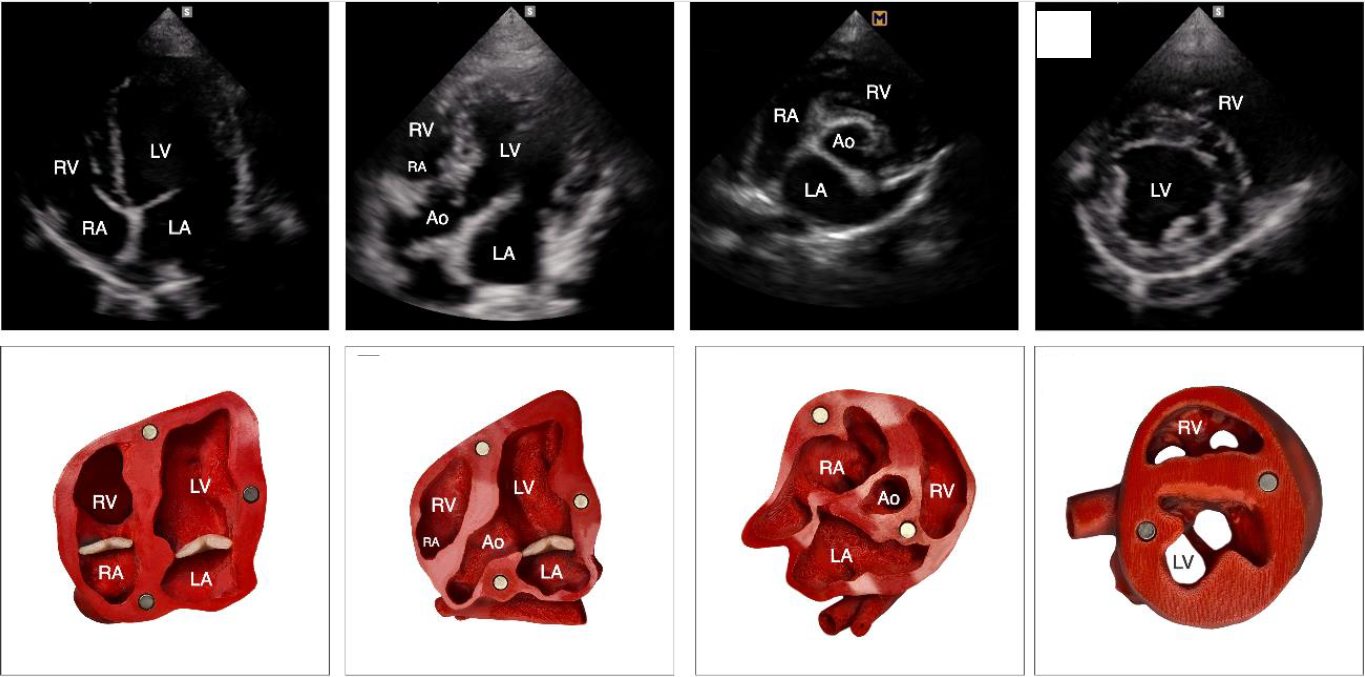

Revolução na Saúde Canina: Como a Impressão 3D Está Transformando a Compreensão dos Exames Cardíacos

ContextoNos últimos anos, a tecnologia de impressão 3D tem revolucionado diversas áreas, incluindo a medicina veterinária. Um estudo recente, que contou com a participação de um dos sócios da Regenera,